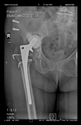

The radiological examination allowed us to verify the close bone-to-implant contact and the unchanged position of the implant during follow-up.

In all the cases operated with the above-described targeting procedure, the stems of the cups remained between the cortical bone surfaces without perforation of the linea terminalis, as shown by postoperative radiographs. There were no complicated surgical situations. In 16 cases, the wound healings were uneventful, and the hips were able to bear weight again after postoperative rehabilitation.

The only patient who suffered an infection healed after the removal of the implant. This complication rate is known and in line with accepted values.

One septic complication occurred. This complication rate is consistent with other revision techniques. In this case, the implant had to be removed, and the patient remained in Girdlestone condition. In such cases, removal of the implants and, of course, surgical debridement and antibiotic treatment are essential. The condition after resection is called Girdlestone’s condition. We had no other complications or unexpected outcomes.